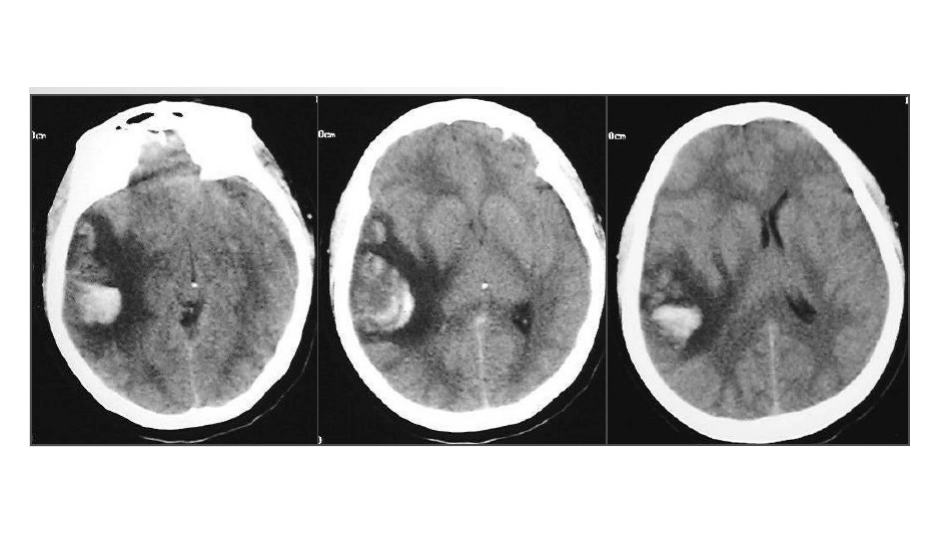

万志文•CVT是一种少见且经常被误诊的卒中类型,年发病率大约为5/100万,占所有卒中的0.5%-1%。CVT更常见于青年个体。•MostadultswithCVTareaged20–50yearsand<10%oftheseindividualsareolderthan65years.Amongyoungandmiddle‑agedadults,CVTisthreefoldmorecommoninwomenthaninmen.•ManifestationsofCVTcanbegroupedintofourdistinctclinicalsyndromes:isolatedintracranialhypertension,focalsyndrome,diffuseencephalopathyandcavernoussinussyndrome如果考虑静脉血栓形成,以下需要做哪些检查?•completebloodcount,•chemistrypanel,•urinalysis,•prothrombintime,•activatedpartialthromboplastintime•genetictestingforthrombophilia•Lumbarpuncture•头颅MRI•头颅CT•catheterangiography静脉窦血栓与静脉窦狭窄、硬脑膜动静脉瘘的鉴别硬脑膜动静脉瘘患者中,有39%~78%合并静脉窦血栓;而无静脉窦血栓的硬脑膜动静脉瘘患者中,78%有静脉窦发育不良、局部狭窄,分隔或变形,考虑静脉窦高压诱发瘘口形成。影像学检查•静脉窦解剖变异使得CT对CVT的诊断不具敏感性,大约仅有30%的CVT病人在CT上有异常所见•上矢状窦后部血栓可以看似一个高密度三角,即高密度或实心的δ(delta)征。•平扫CT也可显示缺血性梗死,有时伴有出血成分。横跨常见动脉分界的(特别是有出血成分的)或紧邻某一静脉窦的缺血性梗死提示CV•蛛网膜下腔出血仅见于0.5%-0.8%的CVT病人•其部位常在大脑凸面,恰与在动脉瘤破裂病人中经常观察到的Willis环区域相反。•MRI对CVT的显示在脑静脉血栓形成的每个阶段都比CT敏感71岁女性,头痛。A.轴位二维T0FMRV显示左侧横窦血流消失(白箭)。B.轴位最大强度投影(maximumintensityprojection,MIP)证实左横窦血流完全消失(白箭头)。C.冠状位MIP对比显示了左、右侧乙状窦和颈静脉窦的管径。横窦不发育或发育不良(白箭头)通常合并同侧乙状窦和颈静脉窦不同程度的发育不良(白箭)。T1加权像显示正常,进一步支持了左侧横窦不发育的诊断52岁男性,头痛伴乏力。A.轴位二维MR静脉成像(TOF)显示左侧横窦(白箭头)和乙状窦(白箭)扩大,窦内无对比剂但可见复杂不均匀低信号影。右侧横窦血流强化正常。B.冠状位MIP重组图像显示左侧横窦血流消失,周围侧支循环开放(白箭头)C.轴位增强T1加权像显示血栓延伸至深静脉系统(黑箭),伴大面积脑实质低信号影,符合颞叶广泛静脉性梗死的表现(黑箭头)D.轴位磁共振梯度回波序列显示双侧颞叶(黑箭头)和深静脉系统血栓形成后,血液信号增高35岁妇女,产后头痛。A.轴位磁共振T1加权像显示窦汇内高信号(白箭)。B.下方层面显示右侧横窦和乙状窦交界处管腔充盈高信号(白箭),提示血栓形成。注意对侧血管的正常流空效应(白箭头)。C.TOFMRV斜冠状位MIP重组图像显示右侧横窦血流消失(白箭),确诊为右侧横窦血栓形成•1.尽管平扫CT或MRI有助于疑似CVT病人的最初评估,但是平扫CT或MRI结果阴性并不能排除CVT。对疑似CVT的病人,如果平扫CT或MRI阴性或在平扫CT或MRI提示CVT情况下为确定CVT的范围,应做静脉造影检查(CTV或MRV)(I类推荐;C级证据)。2.对内科治疗下仍有持续的或演变的症状或有提示血栓扩大的症状的CVT病人,建议早期随访CTV或MRV(I类推荐;C级证据)。3.对表现为提示CVT复发症状的既往有CVT的病人,建议复查CTV或MRV(I类推荐;C级证据)。4.梯度回波T2磁敏感加权成像联合磁共振可能有助于提高CVT诊断的准确性(IIa类推荐;B级证据)。5.对CTV或MRV没有定论但临床上仍高度怀疑CVT的病人,导管脑血管造影可能有帮助(IIa类推荐;C级证据)。6.对病情稳定的病人,为了评价闭塞皮层静脉/静脉窦的再通情况,在诊断后3-6个月时随访CTV或MRV是合理的(IIa类推荐;C级证据)。治疗•一、病因治疗•推荐意见:积极治疗病因,感染性血栓应及时足量足疗程使用敏感抗生素治疗;原发部位化脓性病灶必要时可行外科治疗,以彻底清除感染来源(I级推荐)。•二、抗凝治疗•(1)对于无抗凝禁忌的CVST应及早进行抗凝治疗,急性期使用低分子肝素,成人常用剂量为0.4ml,每日2次皮下注射(180AxaIU/kg.24h);如使用普通肝素,初...